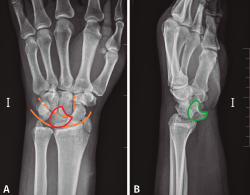

Figura 4. A: radiografía anteroposterior de luxación transestiloperilunar; B: radiografía anteroposterior sin alteraciones, recuerdo anatómico. 1: estiloides radial; 2: estiloides cubital; 3: escafoides; 4: semilunar; 5: piramidal; 6: pisiforme; 7: ganchoso; 8: grande; 9: trapecio; 10: trapezoide; 11: primer metacarpiano; 12-15: segundo a quinto metacarpianos; —: almohadilla grasa; —: eje longitudinal 3.er radio, muñeca y antebrazo; —: arcos de Gilula.

- Qué ver en una radiografía anteroposterior de muñeca (Figuras 4A y 4B). Para valorar que estamos ante una correcta proyección, debemos obtener:

En la radiografía podemos observar los siguientes ítems:

– Pero, en especial, debemos fijarnos en los arcos de Gilula, deben formar 3 líneas continuas, sin disrupciones. En las luxaciones se pierde la continuidad de las líneas que forman los diferentes arcos.

- 1.er arco: superficie proximal del escafoides, semilunar y piramidal.

- 2.º arco: superficie distal del escafoides, semilunar y piramidal.

- 3.er arco: superficie proximal de grande y ganchoso.

• Qué ver en una radiografía lateral de muñeca (Figuras 5A y 5B). Para valorar que estamos ante una correcta proyección, debemos obtener:

Figura 5. A: radiografía lateral de luxación transestiloperilunar; B: radiografía lateral sin alteraciones. Recuerdo anatómico. 1: grande; 2: escafoides; 3: semilunar; 4: cúbito; 5: almohadilla grasa pronadora.

En la radiografía podemos observar los siguiente ítems:

– Debemos prestar especial atención a la congruencia radio-semiulnar-hueso grande. Normalmente los 3 huesos deben formar 3 C alineadas.